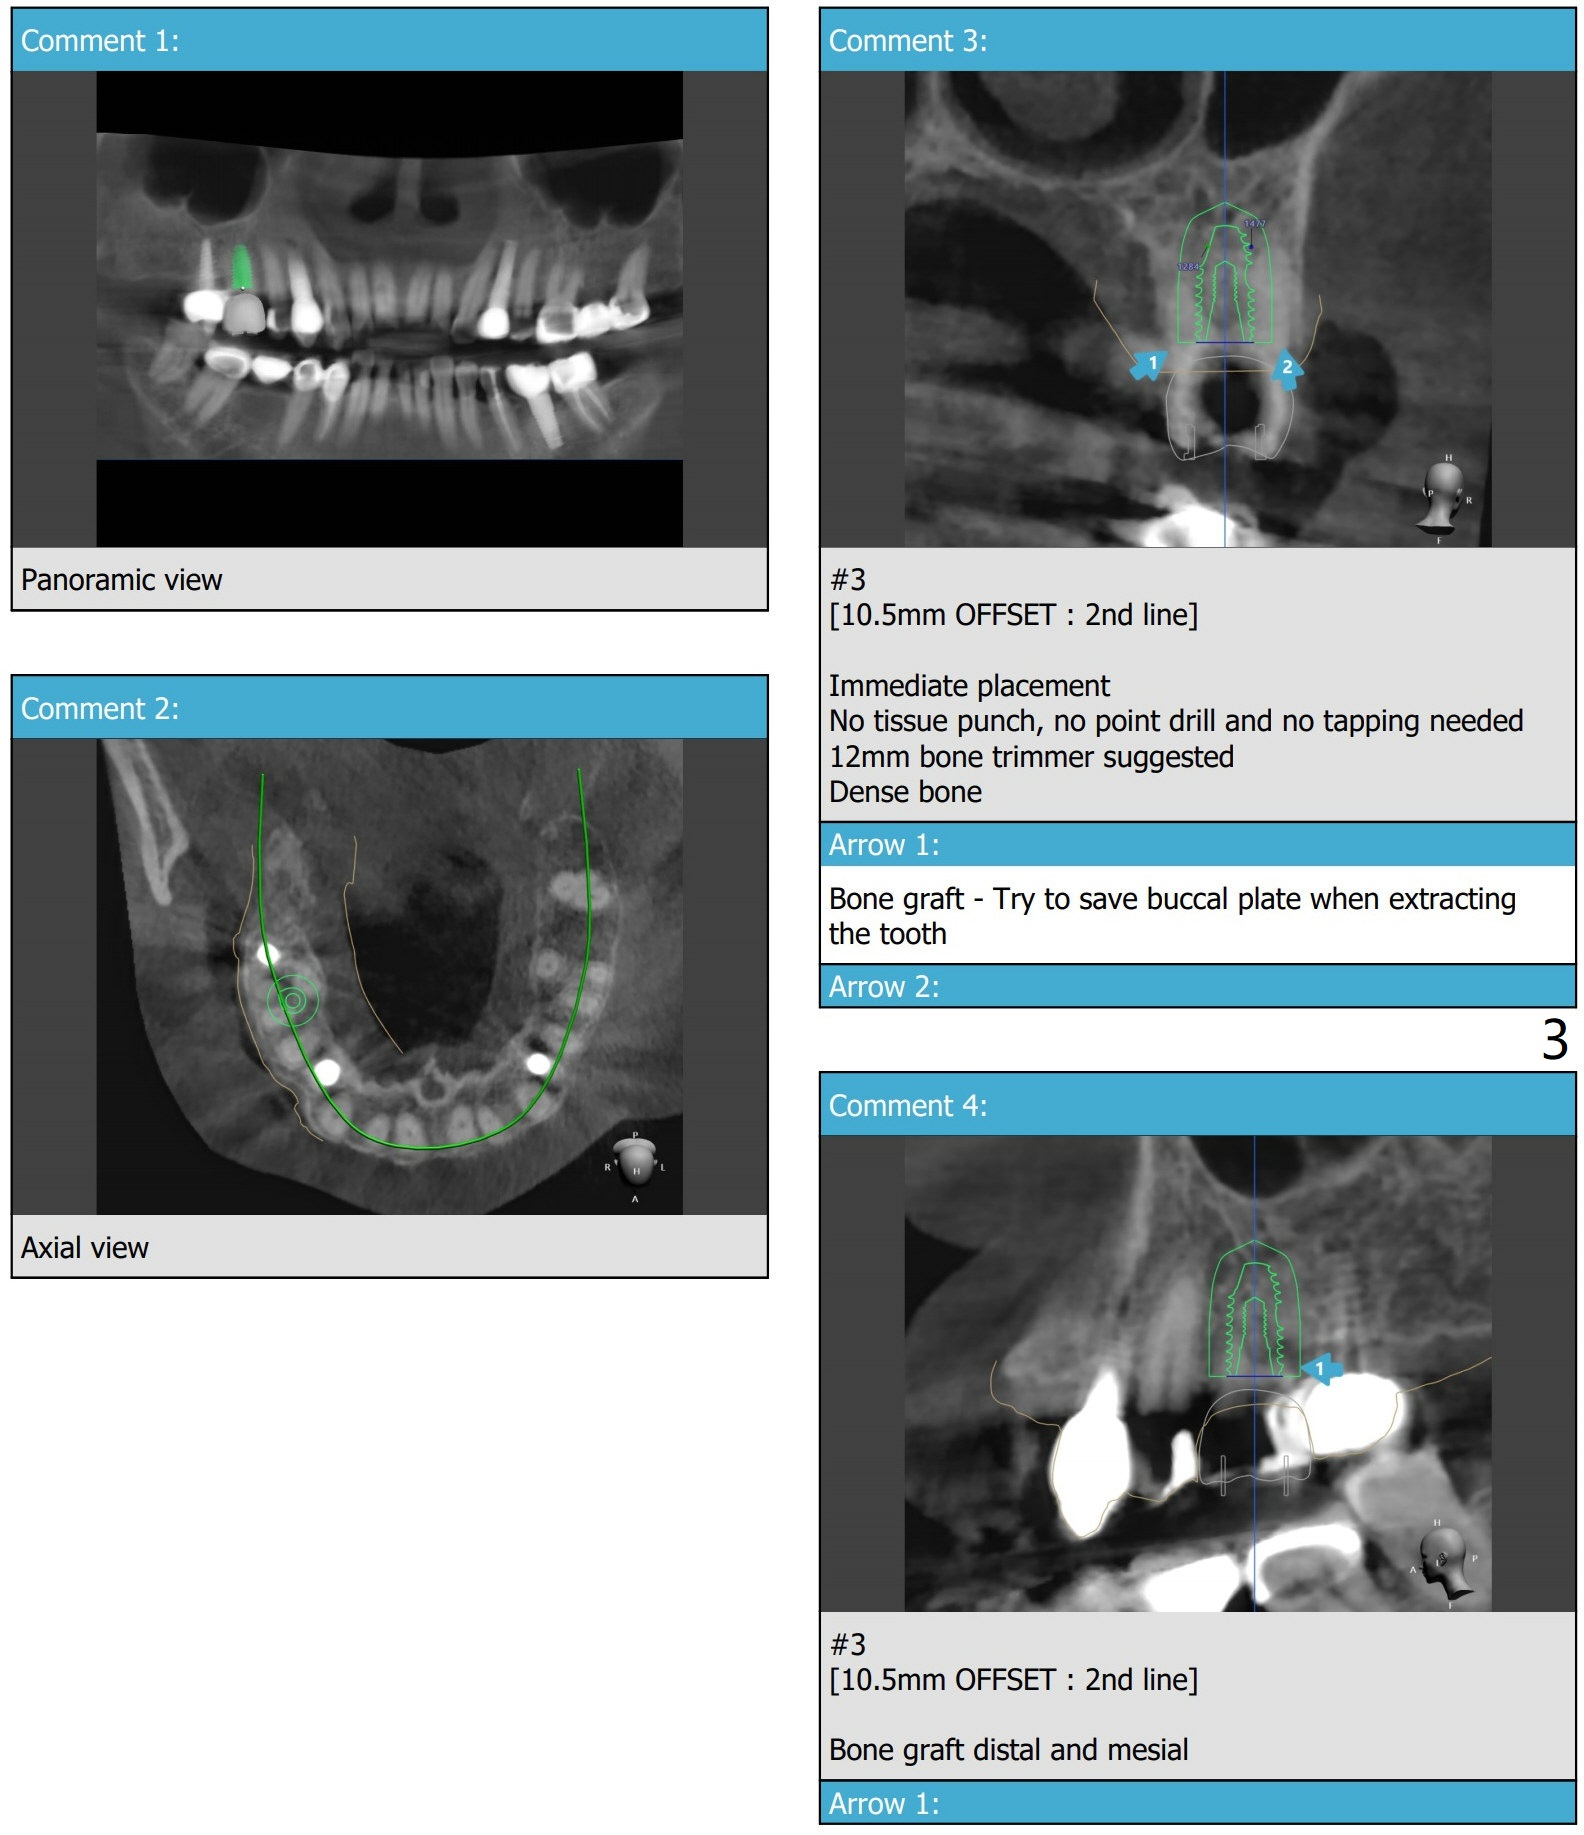

虽然病人骨头宽,但是右上6颊侧骨板薄(图二,三),准备外科手机,切断牙齿,分根拔除。IS dummy implant 4.5x10 and Treatment planning kit to determine the cuff height.